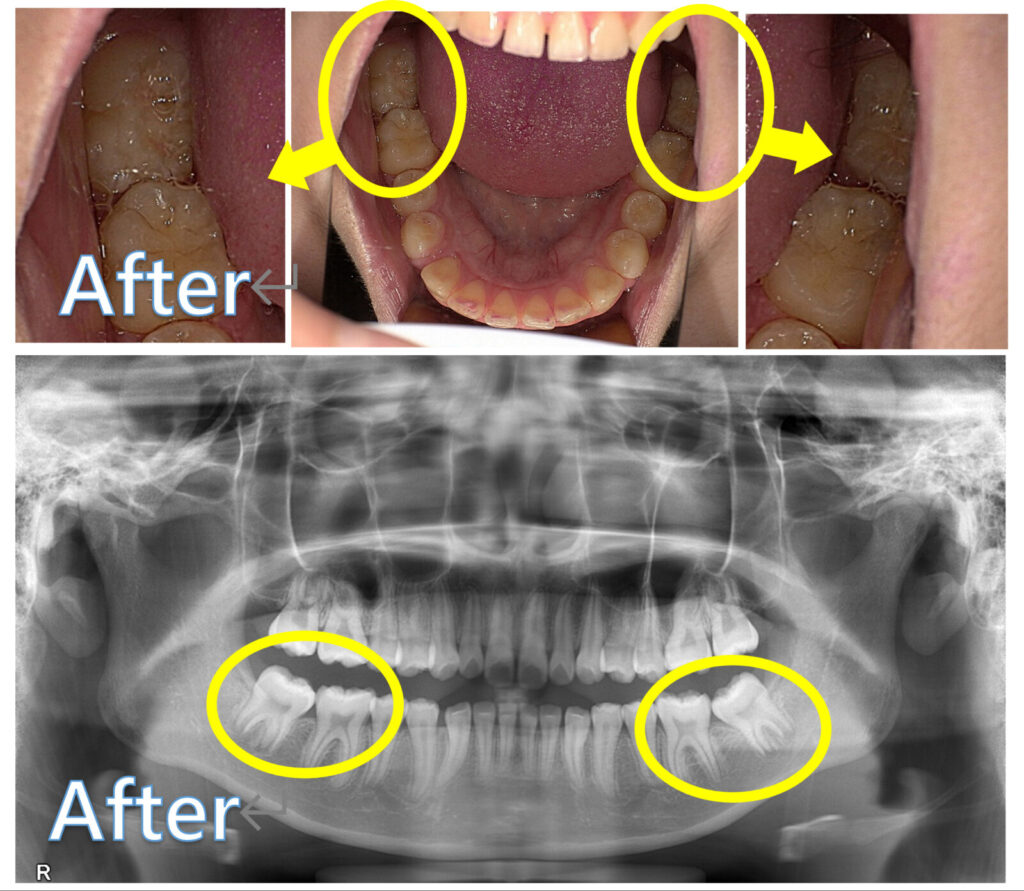

治療開始から6か月後には、12歳臼歯が起き上がってきて、正しい方向へ近づいています。

この患者さんは、臨床上問題ないレベルまで歯が起き上がったタイミングで装置を取り外し、あとは歯の根っこの完成を見守りつつ、上下の歯が噛み合う中での「噛み合わせの完成」を待つことになりました。

装置装着後、右側の奥歯は約3か月、左側も約6か月ほどで生える方向が修正されました。